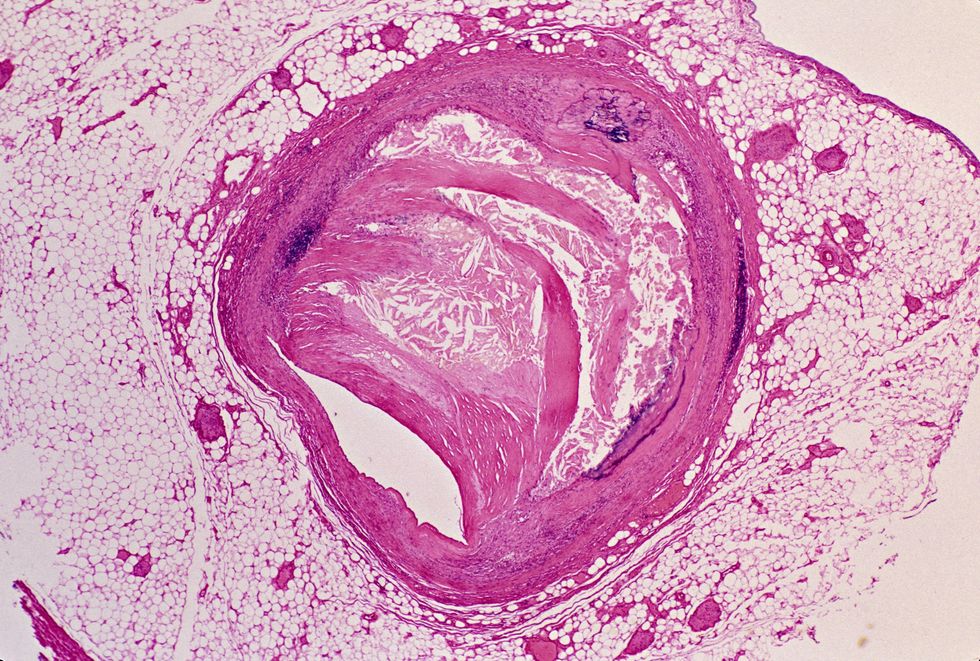

Enlicitide works as a PCSK9 inhibitor, boosting the body's ability to clear LDL cholesterol from the bloodstream.

It's the first drug in this class available as a convenient daily pill rather than an injection.